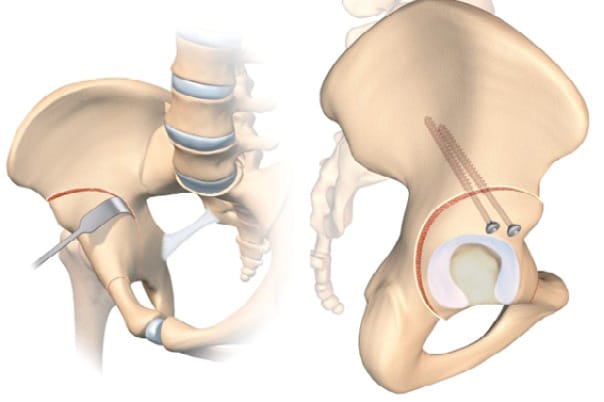

Rotational acetabular osteotomy (RAO) is a technique initially described by Ninomiya and Tagawa in 1984, and it is another surgical strategy for acetabular reorientation, this time practised almost exclusively in Eastern Asia, and mainly in Japan [6] Yasunaga Y, Ochi M, Yamasaki T, Shoji T, Izumi S. Rotational Acetabular Osteotomy for Pre- and Early Osteoarthritis Secondary to Dysplasia Provides Durable Results at 20 Years. Clin Orthop. 2016 Oct;474(10):2145–53. https://doi.org/10.1007/s11999-016-4854-8. It differs from PAO, with a spherical incision that does not disrupt the structure of the pelvic ring. A modified Smith–Petersen approach is used, which offers exposure of the anterior osteotomy in the interval between sartorius and tensor fasciae latae, as well as posteriorly, in a similar way to the Kocher–Langenbeck approach. The osteotomy is performed first with a motorised burr then with curved osteotomes under fluoroscopic guidance, avoiding releasing any fragments of acetabulum that are too fine (risk of necrosis) or creating a gap within the joint. The fragment is mobilised using a hook, fixed with screws and the osteotomy site is repaired with a cancellous bone graft (Figure 5). Another technique making use of a trochanteric osteotomy to improve visibility has been described.

First described by König in 1891, the bone block technique has been adapted and modified by countless authors with an arthroscopic technique recently presented [7], Chiron P, Laffosse JM, Bonnevialle N. Shelf arthroplasty by minimal invasive surgery: technique and results of 76 cases. Hip Int 2007;17 Suppl 5:S72-82. https://doi.org/10.5301/hip.2008.1488[8] Migaud H, Chantelot C, Giraud F, Fontaine C, Duquennoy A. Long-term survivorship of hip shelf arthroplasty and Chiari osteotomy in adults. Clin Orthop Relat Res. 2004 Jan;(418):81–6. https://doi.org/10.1097/00003086-200401000-00014. It involves grafting a fragment of cancellous-cortical bone to the anterosuperior part of the acetabulum to improve bone coverage.

In contrast to the PAO or RAO this strategy increases the size of the acetabulum, similarly to the Chiari osteotomy, which involves metaplasia of the of the capsule and labrum to create a fibrocartilaginous interposition graft.

There are countless options for the approach route, with Smith–Peterson typically being used, although the Hueter anterior approach, minimally invasive medial approach described by Chiron and the Thaunat arthroscopic approach are all possible. The bone graft is taken from the exopelvic part of the iliac crest, and its size is determined preoperatively based on the desired correction. An incision is made at the anterosuperior part of the acetabulum, flush with the capsule, so that the bone block can be placed against the capsule and is stable without fixation. The fragment is then impacted until it is fixed well and/or fixed with screws and/or a plate.

Results have been mixed with 46% survivorship without THA for Fawzy et al and 37% after 20 years in our facility. This is in contrast to Japanese studies with over 70% survivorship with 30 years of follow-up. These results are, however, difficult to compare to those of PAO or RAO because they are used in different populations. In the bone block studies, the largest portion of the population are patients with osteoarthritis, while the advent of modern pelvic osteotomies has been more recent, meaning patient selection has improved, and consequently so have the clinical results. If we look at bone block in the absence of osteoarthritis and subluxation, the survival rate is 81% after 21 years of follow-up [8] Migaud H, Chantelot C, Giraud F, Fontaine C, Duquennoy A. Long-term survivorship of hip shelf arthroplasty and Chiari osteotomy in adults. Clin Orthop Relat Res. 2004 Jan;(418):81–6. https://doi.org/10.1097/00003086-200401000-00014. However, this is a salvage strategy for extremely subluxed or even dislocated hips in which neither PAO nor RAO is possible, nor Chiari osteotomy in view of the risk of the line ending in the sacroiliac joint, preventing medialisation (Figure 6).